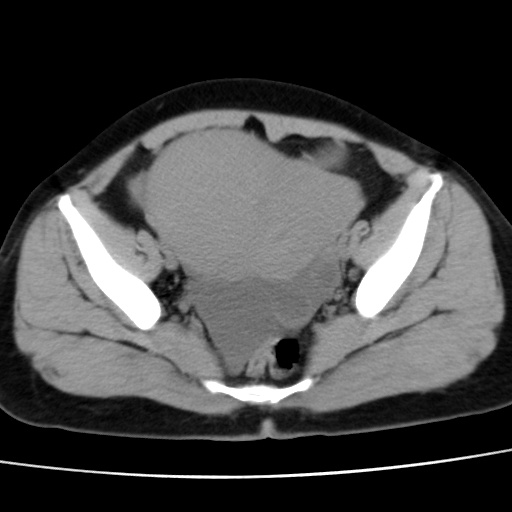

考虑多发子宫肌瘤,子宫直肠窝双囊性占位,另直肠周围脂肪密度增高,不知有何病史

患者因发烧来就诊,查彩超说是子宫颈旁边有无回声区,故来做ct。

子宫肌瘤,宫体部后方见液性密度影,是肠道还是子宫与直肠陷窝积液不好说,我觉得它的位置有点高

患者发热,而子宫直肠窝液性灶有明显边缘且局限且囊性,不除外为包裹性积液或脓肿

1)考虑子宫肌瘤可能性大。2)子宫后方囊性占位性病变,不排除卵巢囊肿可能。

考虑多发子宫肌瘤。子宫后方囊性占位性病变,不排除卵巢囊肿可能。